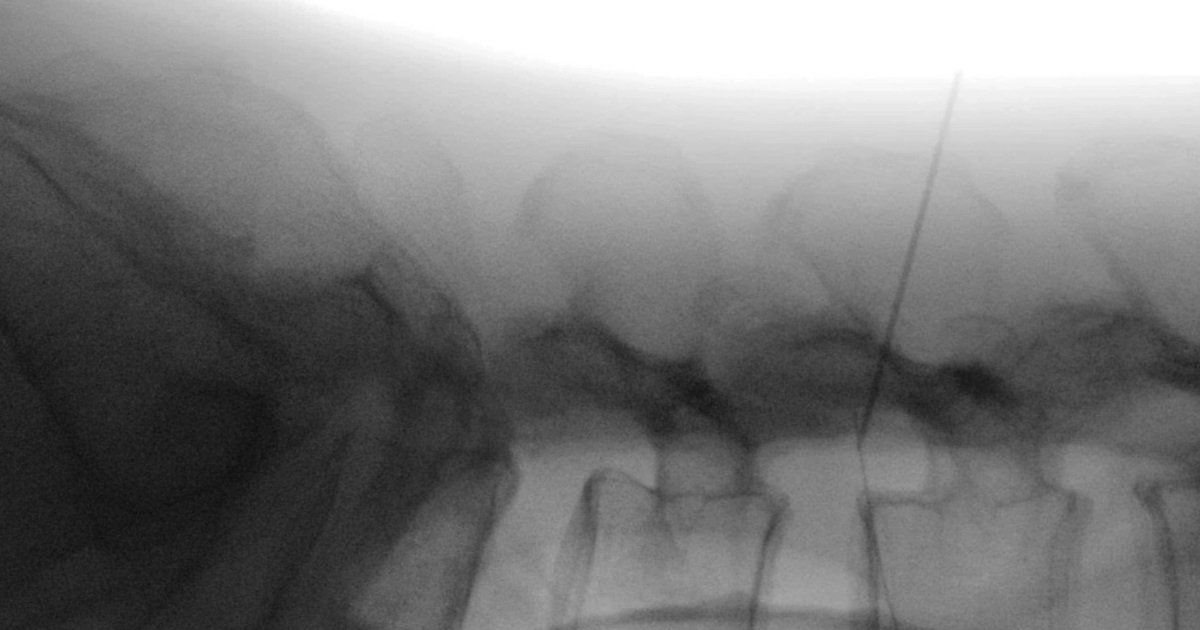

Qua thăm khám lâm sàng, các bác sĩ phát hiện nhiều nốt kim châm xung quanh vùng thắt lưng. Kết quả chụp X-quang phát hiện một dị vật kim khí cắm sâu theo chiều thân đốt sống.

Qua khai thác bệnh sử, bệnh nhân cho biết khi thấy đau ở vùng thắt lưng đã tự dùng kim châm cứu. Một đoạn kim châm dài 6cm đã bị gãy, đâm dọc vào đốt sống của bệnh nhân.

“Một phần của đoạn kim hướng cắm vào ổ bụng, rất may không làm tổn thương các tạng lân cận”, TS.BS Hoàng Thanh Tùng, Chủ nhiệm Khoa Chấn thương Chỉnh hình cột sống, Bệnh viện Quân y 103 cho biết, “Sau khi chụp chiếu và đánh giá, tầm soát các xét nghiệm đủ điều kiện phẫu thuật, chúng tôi đã tiến hành mổ lấy bỏ dị vật cho người bệnh”.

Sau ca phẫu thuật kéo dài 30 phút, các bác sĩ đã định vị chính xác vị trí, tiến hành lấy dị vật ra thuận lợi. Bệnh nhân phục hồi tốt, đi lại bình thường và đã được xuất viện.